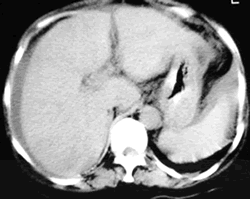

抗核抗体(ANA)、dsDNA、抗可溶性核抗体(ENA)、自身抗体均阴性;抗心磷脂抗体(ACL)(++++);狼疮抗凝物(LA)(-)。乙肝五项:HBcAb(+),余(-);IV型胶原>1000 ng/mL(正常值<140);抗结核抗体(-);PT+A∶1∶1正浆纠正实验:纠正前凝血酶原时间(PT)% 40.3%,活化部分凝血活酶时间(APTT) 48.7s,国际标准化比率(INR) 2.0R,纠正后PT% 57.9%,APTT 31.5s,INR 1.48R。巨细胞病毒(CMV)抗体×2:IgG(+)1∶1024、IgM(+);CMV抗原-PP65×2(-);尿常规:蛋白(-)、硝酸盐及红、白细胞(+);尿沉渣×3:RBC满视野×2,正常形态100%,WBC 1~2/HPF。24小时尿蛋白定量正常;清洁中段尿培养×3:分别为屎肠球菌、 肺炎克氏菌和大肠埃希菌。大便隐血试验(+)。腹水检验为漏出液,细菌培养(-)。腹部CT及B超:肝密度不均,肝脾大(见图),腹水。门静脉彩超:门脉1.0 cm,主干及右支内似可探及极低速血流信号。